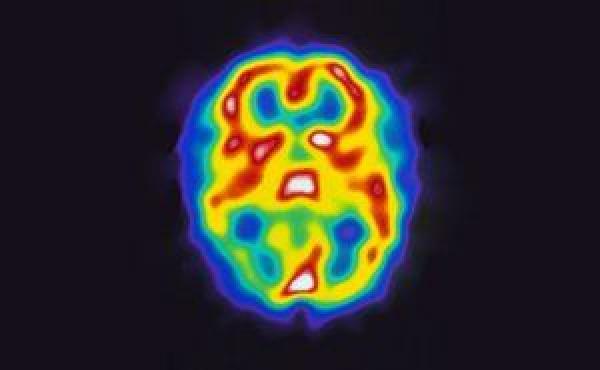

UVA neuroscientists have discovered that an unexpected form of cellular cleanup takes place in developing brains. If this process goes wrong — happening too little or too much — it can cause permanent changes in the brain’s wiring. In lab mice, this results in anxiety-like behavior, and it may play a role in neurological conditions such as autism in humans.

The cellular cleaner the researchers spotted, the AIM2 inflammasome, has been associated primarily with the body’s immune response to infections but has not been extensively studied in the brain. But there it plays a critical role in ensuring the developing brain is assembled properly and functions correctly, Lammert discovered in collaboration with principal investigator John Lukens, PhD.

“Neurodevelopment is a very complicated process,” said Lammert, a graduate student whose specialized skills were instrumental in the discovery. “This form of cell death actually plays a role in removing unwanted cells from the brain to establish a healthy CNS with the correct connections and the right number of cells.”

More than half the neurons created during brain development end up dying, so proper cleanup is essential, noted Lukens, of UVA’s Department of Neuroscience. “Too much or too little is thought to underlie everything from autism to intellectual disability — any type of neurodevelopmental disorder,” he said.